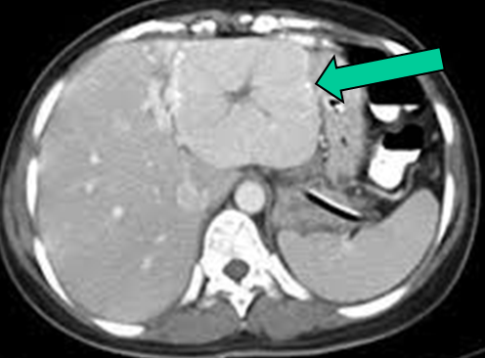

- Görüntüləmədə I seqment hipertrofiyası (yüksək şübhə əlaməti)

- Diaqnozu dəqiqləşdirmək üçün Qc venaları yoxlanılmalıdır. Bunun üçün dopler USM, KT-angioqrafiya, MRT-angioqrafiyalar və ya kontrastlı venoqrafiya edilir.

- Görüntüləmədə Qc venalarının trombotik tutulması diaqnozu dəqiqləşdirən əlamətdir.

- Görüntüləmədə qaraciyər venalarının tıxanması

Baddi-Kiari sindromu böyük qaraciyər venalarının tıxanması nəticəsində meydana gələn venoz durğunluqdur, qaraciyər venaları ilə yanaşı aşağı boş venada da tıxanma ola bilir. Tromboz, fibroz, membran və infiltrasiya (şişlər, iltihab) ən çox rast gələn səbəbləridr. Erkən mərhələlərdə kəskin hepatit və kəskin qaraciyər yetməzliyi, xroniki mərhələdə sirroz və PH meydana gələ bilir. Diaqnozu üçün tomoqrafiya və kontrastlı angioqrafiya lazım gəlir, Qc venalarının trombotik tutulması diaqnozu təsdiqləyir. digər xarakterik əlaməti birinci seqmentin hipertrofiyasıdır. Erkən mərhələdə dekompressiya (cərrahi və stend) sirroz əmələ gəldikdə isə transplantasiya ön planda tutulur.

Qaraciyər venalarının görünməməsi, kontrastlaşmaması və ya trombla tıxanması.

- Görüntüləmədə qaraciyər venalarının tıxanması, I seqment hipertrofiyası ola bilər (xroniki forma);